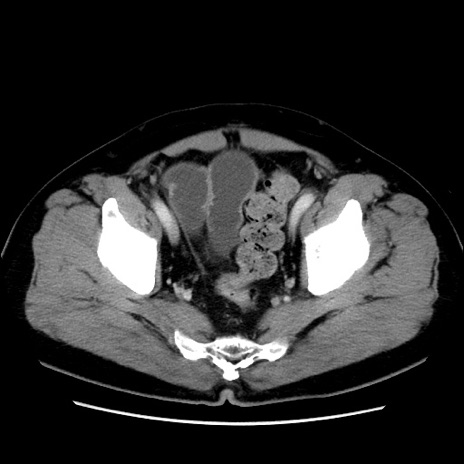

症例16(横断像)

【症例】 70歳代男性

【主訴】 腹痛、嘔吐

【現病歴】 約1ヶ月前より間欠的に腹痛と嘔吐あり、当院消化器内科を受診したところCTで多発する肝臓のLDAを指摘され、精査中であった。以降は消化器症状は安定していたが、2日前より嘔気と腹痛があり、同日より排便・排ガスが消失した。改善認めず、 本日、救急外来を受診した。

【既往歴】 大腸ポリープ切除後。

【身体所見】意識清明・会話良好、BT 36.3℃、BP 127/80mmHg、 P 80bpm、腹部:膨満あり、平坦・軟、上腹部正中および下腹部正中に圧痛あり、反跳痛なし、筋性防御なし。

【データ】WBC 7200、CRP 0.77